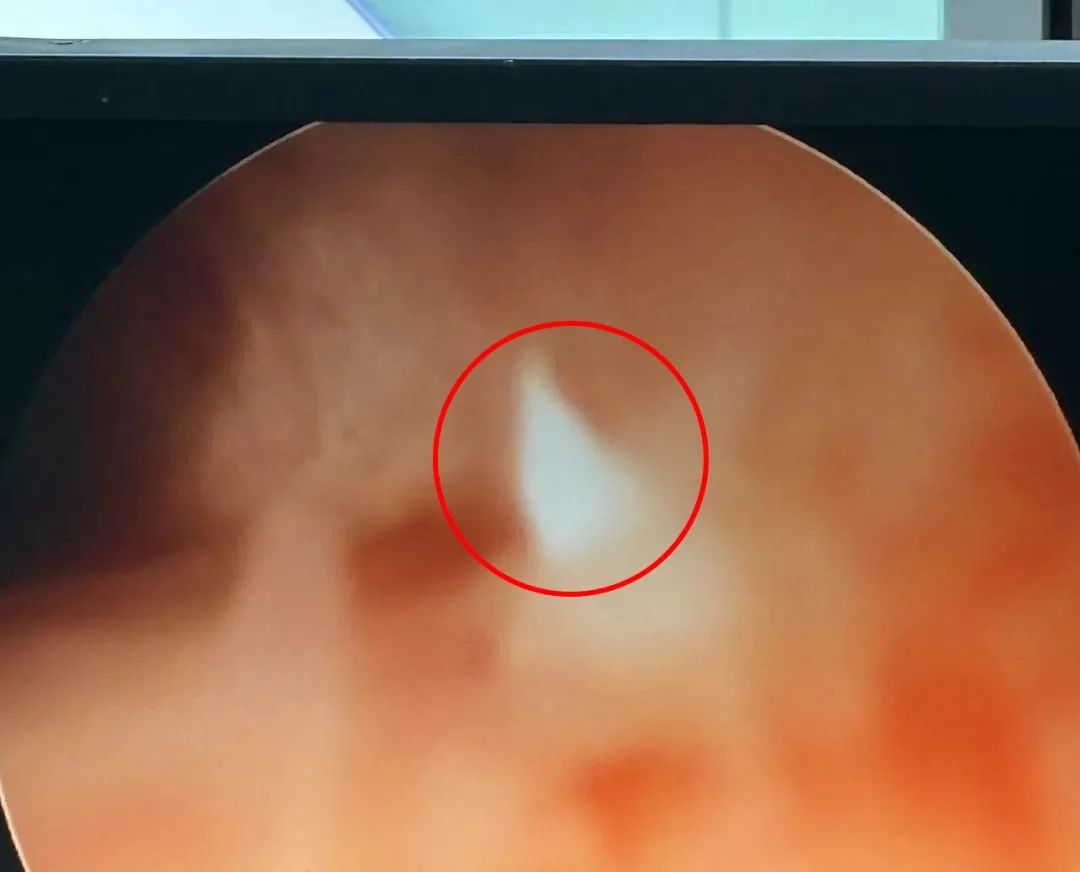

在进行充分的术前准备后,沈兰兰主任带领团队开始实施宫腔镜子宫内节育器取出术,术中探查在宫颈管左后壁见突出1mm节育器残端(见下图-左),其余部分完全嵌顿在宫颈管肌层内,沈主任通过准确定位后,先用冷刀器械分离周围组织,显露出残留节育器断端,而后用取环器在宫腔镜阴道下成功取出T型节育器残端,长约2cm(见下图-右),见表面包裹金属材质,无活动性出血,术后安返病房。